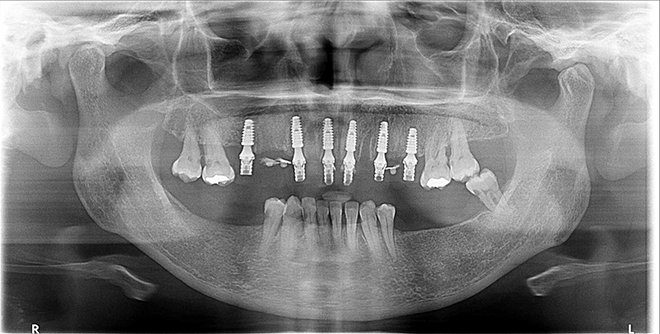

Após o planejamento integrado cirúrgico-protético do caso, foram realizadas exodontias dos elementos 13 a 23, 15, 24 e 25, sendo imediatamente instalados seis implantes Implacil Due Cone com 11 mm de comprimento e 3.5 mm de diâmetro (Implacil De Bortoli), com precisão no posicionamento tridimensional do implante. Visando o condicionamento gengival e a formação de um perfil de emergência adequado, após a instalação de mini pilares Implacil com cinta de 4.5 mm, foi instalada uma prótese fixa provisória imediata (Figura 4). Após dois meses, uma radiografia panorâmica foi realizada para verificar a osseointegração dos implantes (Figura 5), visando o início da reabilitação protética definitiva.